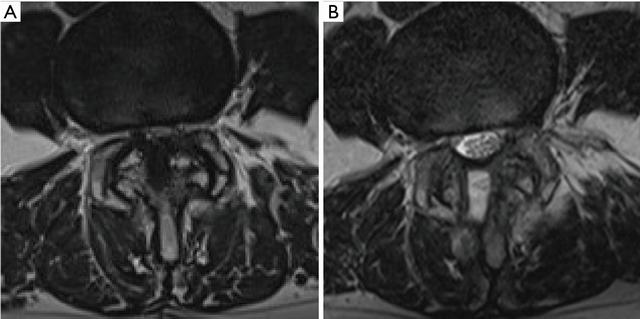

UBE减压后,狭窄的椎管明显扩大,在MRI上最狭窄的轴向图像上测得的硬脊膜横截面积CSDA从71.4±36.5 显着增加到177.3±59.2 平方mm(P <0.005,配对t检验)。CSDA平均增加105.9±39.5平方mm,比术前增加201.9%±188.0%。切口侧小关节保存的百分比为84.2%±9.3%,对侧为92.9%±6.2%(P = 0.024,配对t检验)(图6)。

图6 UBE减压后末次随访MRI(B)和术前MRI(A)的比较显示,对于严重腰椎管狭窄的患者,UBE对椎管减压充分,硬膜截面积得到改善,双侧小关节获得保留。

UBE减压技术可以实现足够的减压。本研究中,平均硬脊膜横截面积CSDA从71.4增加到177.3平方mm,增加201.9%。手术后临床数据也显示出很大的改善,腿部疼痛VAS评分从7.3降低到仅0.9。患者的神经系统症状和残疾状况也有明显改善,这反映在JOA评分和ODI的改善上,使用改良的MacNab标准评估优良率超过90%。

在脊柱的后柱稳定结构中,小关节复合体是最重要的。生物力学测试表明,超过50%的小关节破坏会导致脊柱节段不稳定,所有的微创手术方法旨在获得充分椎管减压的同时尽量保留小关节复杂的完整性。UBE通过内窥镜检查方法,可以将外科医生的视点推进到椎板内部或对侧侧隐窝,因此可以最大程度保留小关节。如果使用30度内窥镜,视野将更广泛。本研究中发现,UBE椎管减压足够充分的同时,小关节也得到了很好的保留,切口入路侧小关节保留率为84.2%,对侧为92.9%。